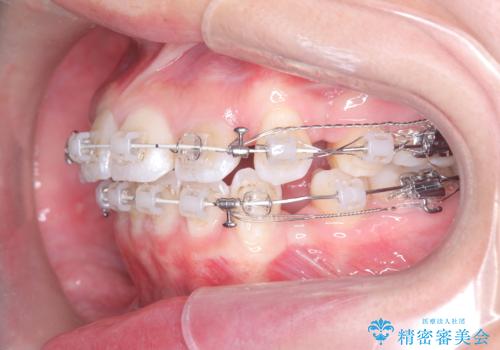

治療は、審美ワイヤーを用いて抜歯スペースを徐々に閉じながら、前歯の角度と位置を精密にコントロールして進められました。ワイヤー矯正は歯を三次元的にしっかりと動かすことができるため、前歯を単に倒すのではなく、根元から理想的な位置へと誘導しました。

1年半の治療期間を経て、抜歯したスペースは完全に閉じ、突き出ていた前歯はすっきりと内側に収まりました。噛み合わせの精度も向上し、機能面でも良好な結果が得られています。